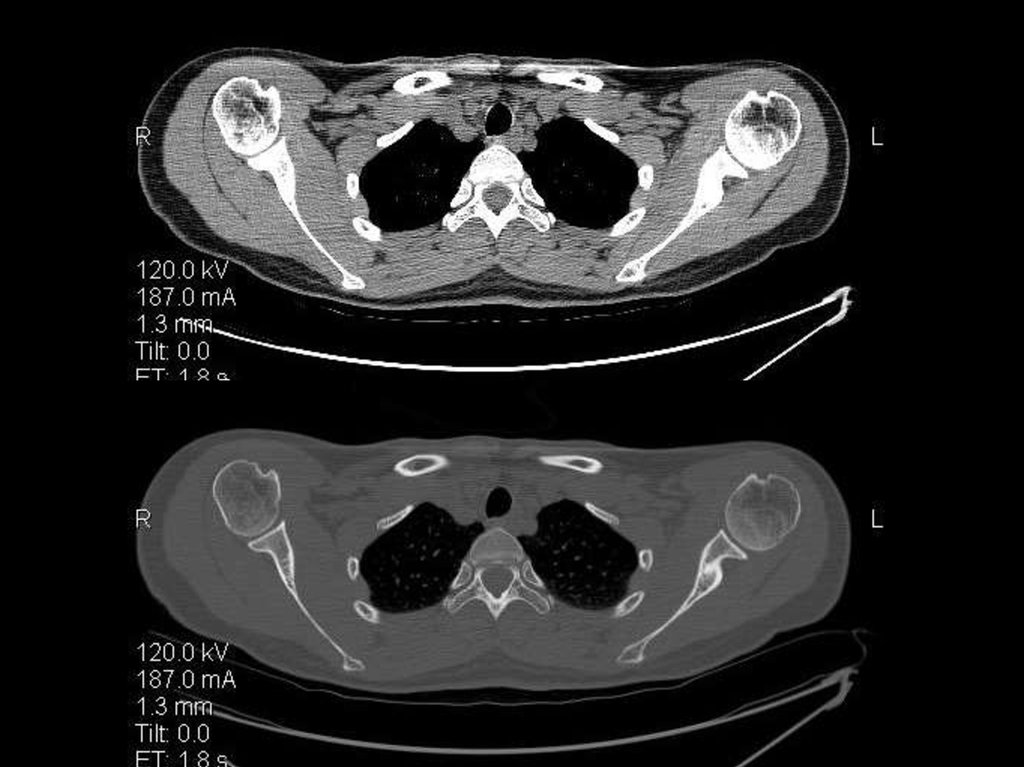

исследование плечевых суставов

23.

24.